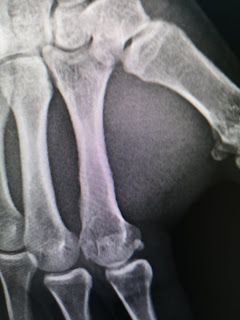

Daca sunteti curiosi, asa arata la 8 zile radiografia.

Va zic eu, e bine. Vedem la 21.